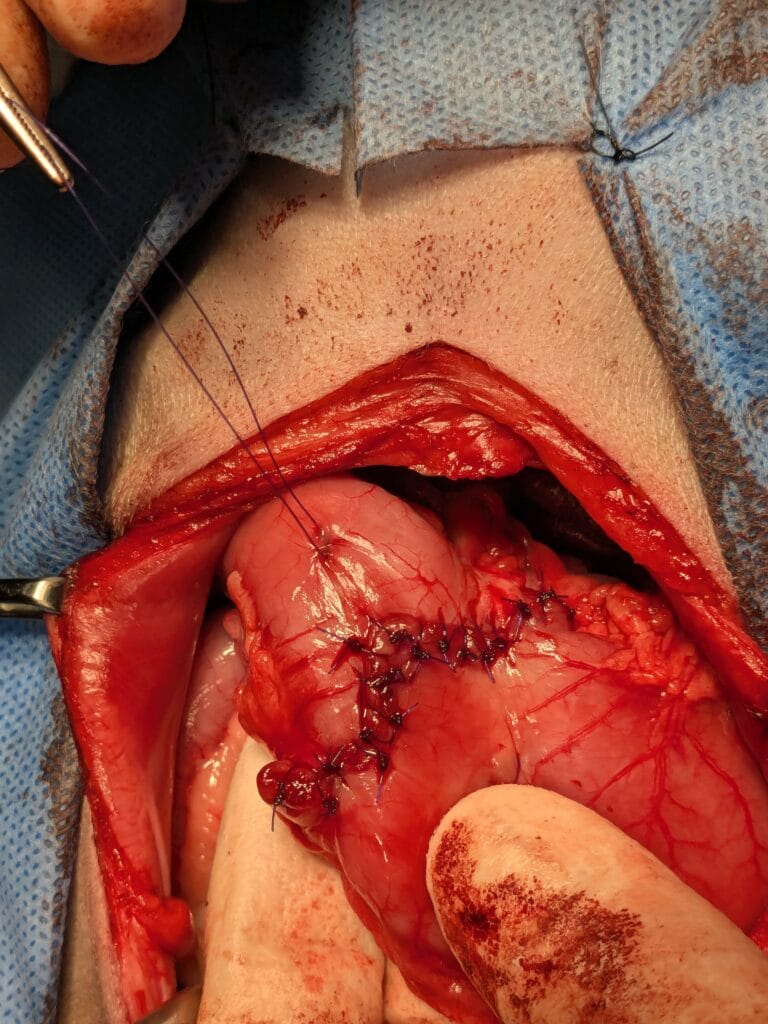

今回行ったのは幽門形成術(Y-U形成術)です。

幽門部をY字状に切開し、U字状に縫合することで内腔を広げる手術です。

手術写真です。

胃をY字状に切開したところです。わかりづらいですが、ピンセットで示しているところが幽門部の内腔です。肥厚しており、十二指腸につながるスペースがありません。

内腔の粘膜を切除し、縫合して終了です。